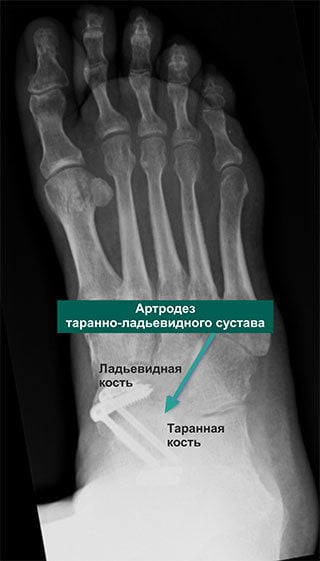

Хирургия

Если консервативная медицина остается бессильной перед артрозом таранно-пяточного сустава, то больному приходится соглашаться на хирургическую операцию. Этот вид лечения показан при заболевании последней стадии, когда дистрофия сочленения стала необратимой. Решение о проведении операции принимает врач.

Хирургическое лечение позволяет получить хорошие результаты: устраняет боль и возвращает пациента к обычной повседневной жизни. Суть оперативного вмешательства состоит в удалении из сустава всех поврежденных дистрофией фрагментов и создании благоприятных условий для его последующего сращивания. Операция проводится под общим наркозом.

Многих пациентов пугает мысль, что стопа после хирургического вмешательства будет полностью обездвижена. Но вопреки всем страхам при правильном восстановлении человек, страдающий много лет артрозом, сможет полноценно жить, заниматься спортом, вести активный образ жизни без боли и практически без хромоты.

Осложнением операции может стать формирование ложного сочленения. Такое возникает тогда, когда кости друг с другом не срастаются. Потребуется повторная операция с дополнительной костной пластикой для быстрого заживления.